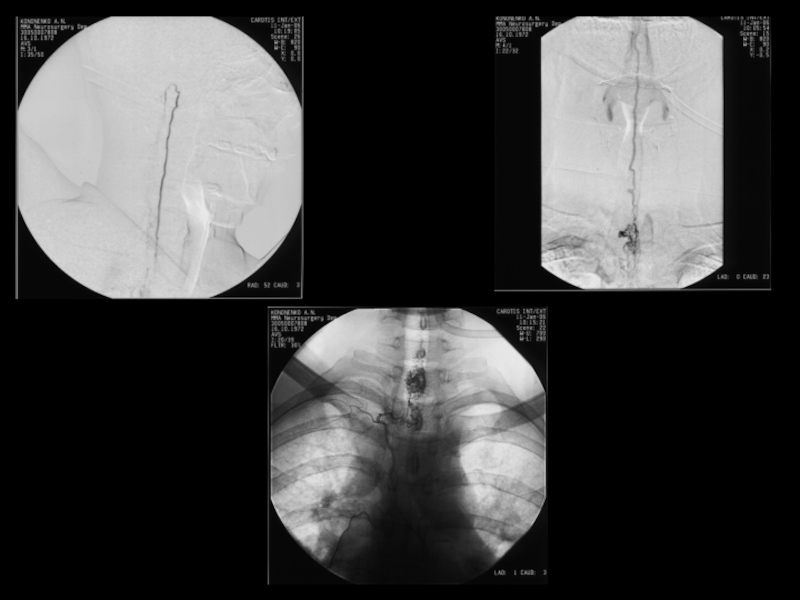

Слайд 33Нейробластома

Нейробластома